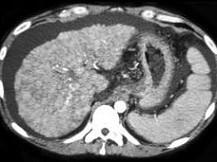

问题 男,15岁,进行性肢体震颤,肌张力增高,实验室检查尿铜125μg/g,CT检查如图,应诊断为 ( )

选项 A、肝血色素沉着症 B、结节性肝癌 C、肝硬化 D、肝转移瘤 E、肝豆状核变性

答案 E